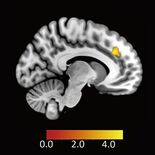

・脳MRIで評価された患者(n=14)の間では、無症候性大脳病変(DWI+/FLAIR+)は観察されなかった